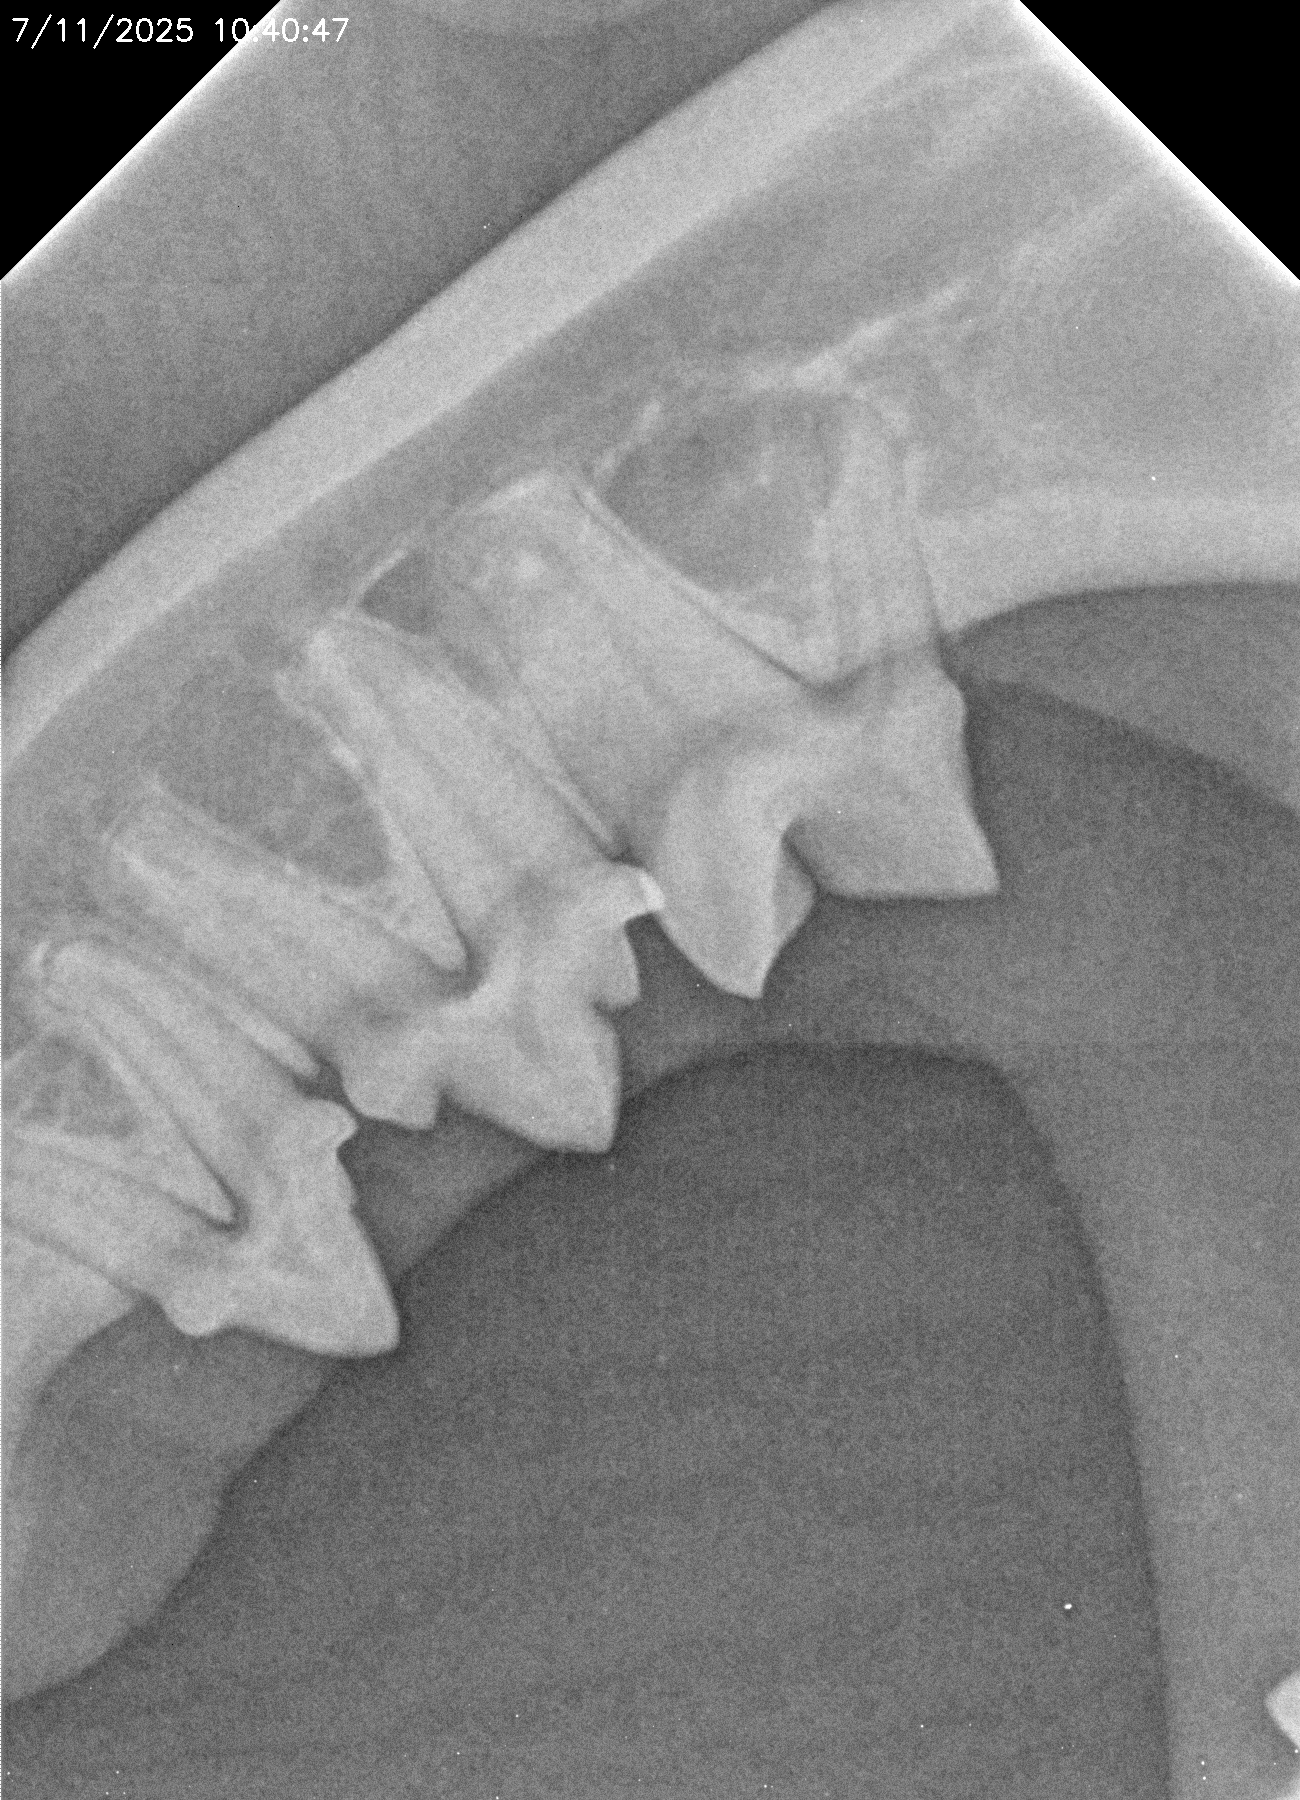

La salud bucal en animales es fundamental para su bienestar general. Los problemas dentales más comunes, como las infecciones bucales, las encías inflamadas o los dientes en mal estado, no solo provocan mal aliento y dolor, sino que pueden causar complicaciones más serias. Cuando se dejan sin tratamiento, las bacterias orales pueden llegar al torrente sanguíneo y afectar órganos importantes como el corazón, los riñones y el hígado.

Al igual que en los humanos, la higiene dental regular es esencial para prevenir enfermedades periodontales y otros problemas dentales. Los animales que sufren de dolor bucal pueden volverse más irritables, perder el apetito y, en algunos casos, experimentar dificultades para comer o masticar.